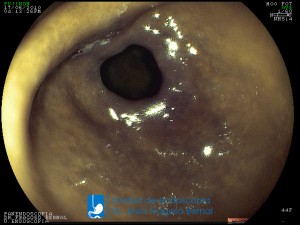

La Unidad de Endoscopía fue creada en 2002 por el Dr. Jesús Fragoso Bernal, es pionera en el estado por la utilización de la tecnología más avanzada, que nos permite ofrecer servicios integrales de diagnóstico y tratamiento para las enfermedades del aparato digestivo.